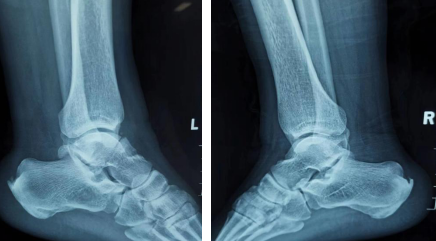

自3月28日以来,徐州市疫情形势紧张,抗疫人员肩扛重担,投身疫情防控工作中。4月8日,徐州县区一抗疫人员在工作中意外受伤,伤后即感双足跟肿痛、畸形、活动受限,在当地医院行拍片检查提示:左距骨骨折。

随后,患者来到betway在线登陆,他告诉接诊医生,右足负重行走时有疼痛感,行进一步检查显示右跟骨骨折,急诊拟“左距骨骨折、右跟骨骨折”将患者收治入院。

术前X线